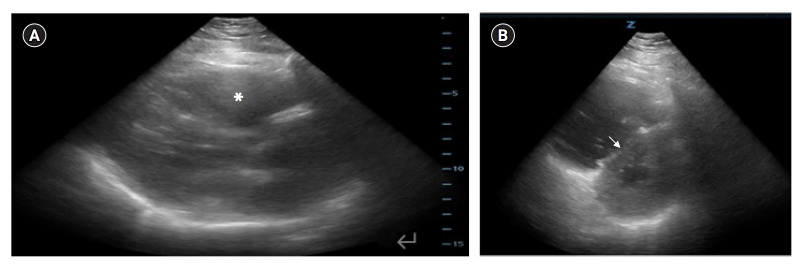

Extracorporeal membrane oxygenation (ECMO) has been increasingly employed in the emergency department for patients with a potentially reversible cause of cardiac arrest. We present the case of a young female patient with an in-hospital cardiac arrest who was found to have severe right heart strain on point-of-care ultrasound (POCUS), suggesting a massive pulmonary embolism. Rapid bedside diagnosis using ultrasound expedited bedside cannulation and initiation of ECMO as a bridge to surgical thrombectomy, and ultimately the patient survived with full neurologic function. With its ready availability and increasing acceptance by consultants, POCUS should be incorporated into cardiac arrest algorithms as the standard of care to rule in thrombotic and obstructive causes of cardiac arrest.

Abstract Image